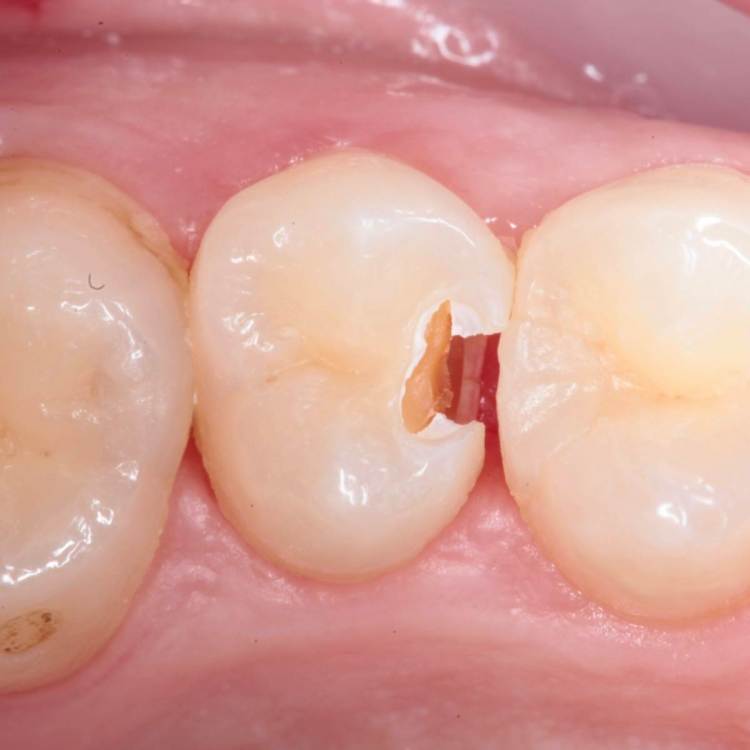

Глубина полости ниже уровня десневого края на 2-3 мм. Коагуляция, ENDO, анатомичный билдап, проверка качества реставрации и отсутсвие нависающего края (интерпроксимальный снимок), рекомендации.

Доступ проводился шаровидным бором, синим финиром и аналогом бора endo z.